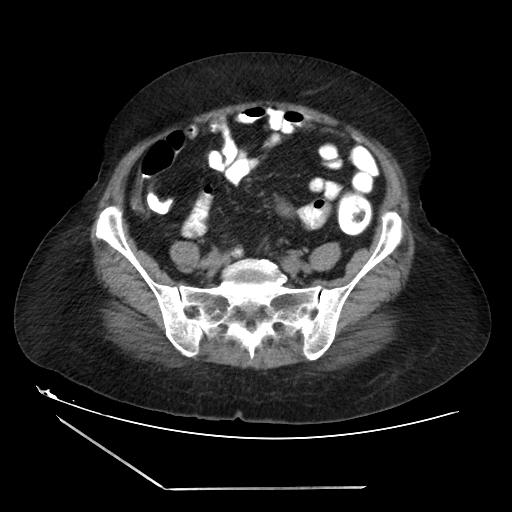

A 70 years old woman with Obstractive jaundice & palpable GB